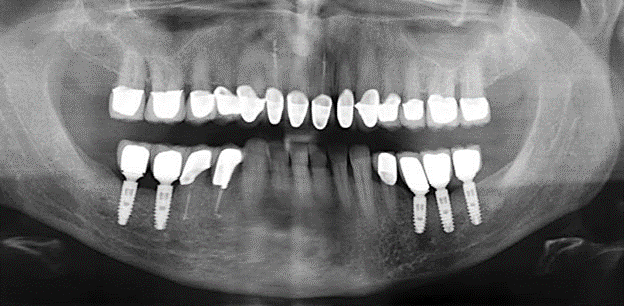

Für den klinischen Langzeiterfolg des parodontal kompromittierten Patienten ist die standardisierte und regelmäßige risikoadaptierte Betreuung im Rahmen der UPT der zentrale Baustein des Behandlungserfolgs. Dies gilt in besonderer Weise für Patienten, die nach erfolgreich abgeschlossener parodontaler Sanierung mit Implantaten versorgt wurden (Abb. 11a und b).

Vor Beginn der prothetischen Versorgung ist es ratsam, den Patienten über die im Rahmen der UPT erforderlichen zeitlichen und finanziellen Aufwendungen (zwei bis viermalige UPT pro Jahr, lebenslang) zu informieren. Dies trägt wesentlich dazu bei, die Compliance des Patienten zu sichern. Darüber hinaus ist die Praxis bei der Bereitstellung der räumlichen und personellen Ressourcen für die Betreuung der parodontal sanierten Patienten gefordert.